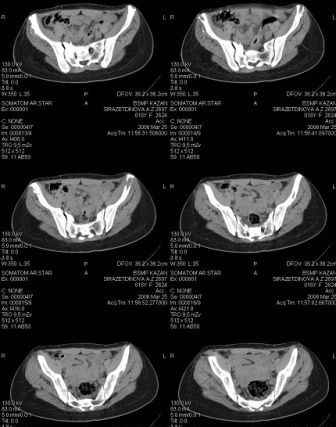

Предоставляю срезы. Если пациентку функционально ничего не беспокоит, стоит ли навязывать ей лечение.

Для уточнения диагноза ниеобходимы обзорные рентгенограммы таза (прямая и inlet), Кт срезы на уровне переломов для определения степени сращения и решения вопроса о методе оперативного восстановления анатомии (делать ли остеотомию, низводить ли задние отделы), ни о какой "остеотомии выступающих отломков" тем более у девочки 18 лет речи быть не может.